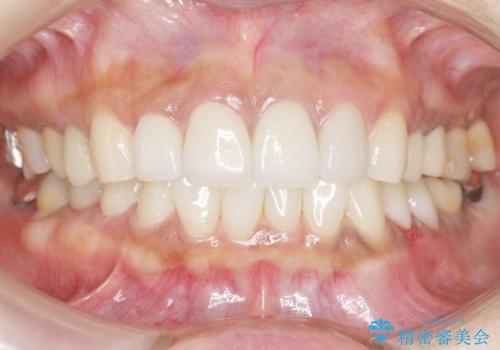

- 前歯のセラミック治療から5年経過した患者様です。

数年ぶりにメンテナンスに来て下さいました。

治療した上の前歯4本は全く問題がないそうで、「どうしてこんなに長持ちするんですか?」と聞かれた程です。

5年前のクラウン装着時と比較したところ、歯肉が成熟し歯間乳頭ができており、より天然歯のように自然に見えました。

患者様の良好なセルフケアと精密な適合の良いクラウンにより、歯肉の腫脹や退縮も認められませんでした。